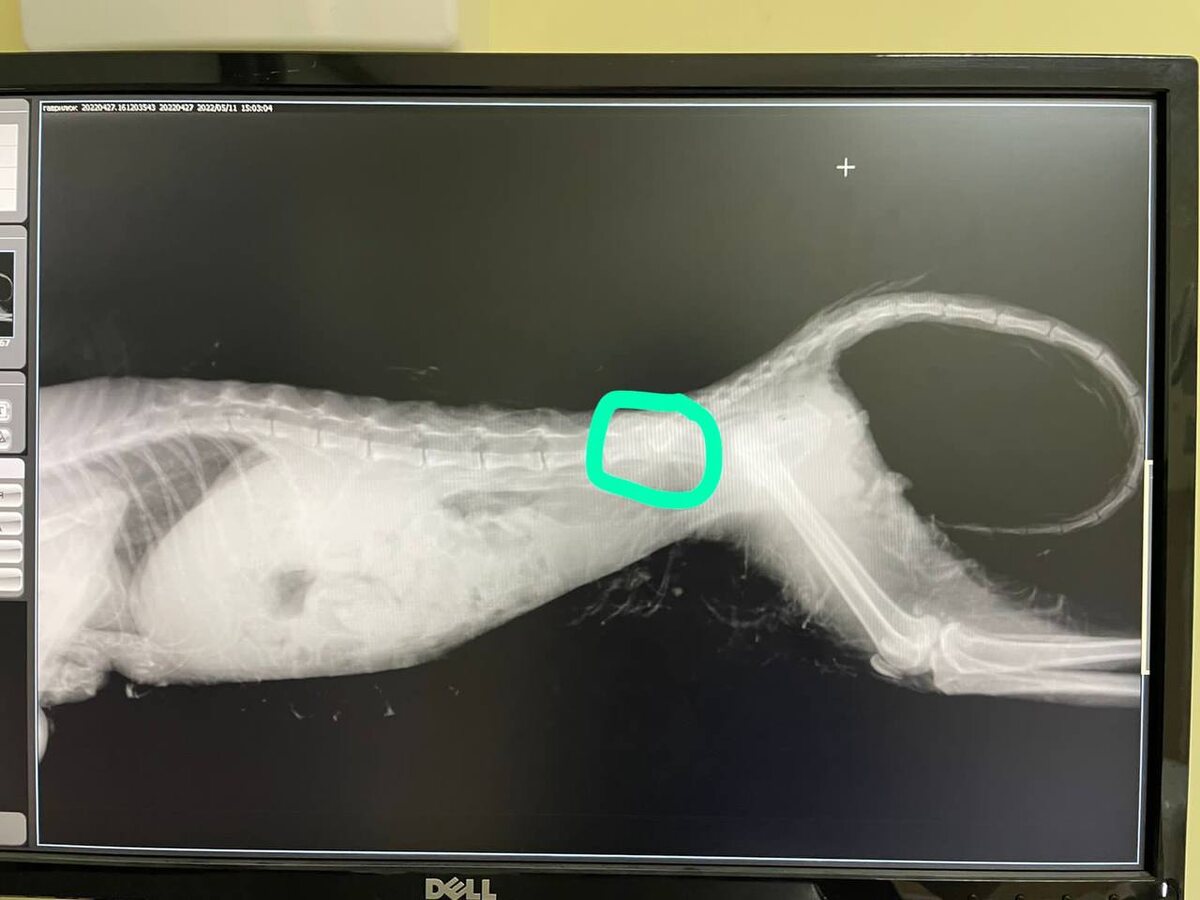

Лаура не бегала, не прыгала и не ловила мышей. После травмы позвоночника её задние лапы навсегда потеряли подвижность. Врачи говорили: «Это слишком сложно. Ходить она уже не будет. Никогда». А те, кто принес ее в клинику, решили, что эвтаназия это высшая милость для нее. Но в тот день вы решили иначе.

Фото-история: